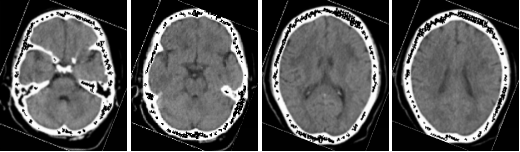

1、中樞神經(jīng)系統(tǒng)

病例一 男,53歲, 突發(fā)右側(cè)肢體力弱, 言語(yǔ)不清, 伴惡心嘔吐、 伴頭暈頭昏、 伴視力模糊, 無(wú) 意識(shí)障礙、 無(wú)面癱。

CBT CBV MTT DLY TTP

從圖中CTA可見(jiàn)左側(cè)大腦中動(dòng)脈M 1段閉塞。

腦灌注所示左側(cè)大腦中動(dòng)脈供血區(qū)DLY、 TTP、 MTT時(shí)間顯著延長(zhǎng),CBF略減低, 考慮為 急性腦梗死; 左側(cè)額葉、 頂枕葉CBF、 CBV顯著減低, 符合軟化灶表現(xiàn)。

經(jīng)大動(dòng)脈腦血管造影+機(jī)械血栓清除+動(dòng)脈內(nèi)溶栓術(shù), 顯示血管病變位置與CTA顯示病變 位置相符, 治療后, 該血管供血區(qū)域得到明顯改善。

核磁共振檢查證實(shí)梗死核心區(qū)域與灌注圖所示區(qū)域匹配。

患者術(shù)后復(fù)查腦血管灌注一站式檢查, 腦血管CTA顯示原閉塞的左側(cè)大 腦 中 動(dòng) 脈M 1段 此 次 顯 影 通 暢 , 局 部 中 度 狹 窄 。 腦 灌 注 分 析 顯 示 左 側(cè) 額 葉 及 頂 枕 葉 軟 化 灶 改 變 , 基 本 同 前 ; 原 左 側(cè) 的 大 腦 中 動(dòng) 脈 供 血 區(qū) 大 面 積 灌 注 異 常 較 前 明 顯 改 善 。2 0 1 8 - 1和 2018 - 5月兩次復(fù)查, 都顯示原堵塞血管通暢, 與溶栓后對(duì)比無(wú)明顯變化。

640層寬體探測(cè)器CT為16 cm覆蓋不動(dòng)床一站式神經(jīng)成像, 通過(guò)一次注藥, 一次掃描可以 獲得完整的純動(dòng)脈期、 純靜脈期和腦血流功能灌注成像及動(dòng)態(tài)CT- DSA電影圖像, 每一個(gè)動(dòng) 態(tài) 數(shù) 據(jù) 都 是 在 同 一 時(shí) 相 獲 得 , 同 時(shí) 包 含 了 解 剖 和 功 能 的 信 息 , 通 過(guò) 對(duì) 神 經(jīng) 一 站 式 的 快 速 分 析, 在60 秒內(nèi)就可以完成急性腦卒中的全面評(píng)估。

不動(dòng)床的采集模式避免了螺旋穿梭式灌注帶來(lái)的全器官不在同一時(shí)相采集、 連續(xù)曝光劑 量大的不足; 獨(dú)有的SVD+算法帶來(lái)精準(zhǔn)的灌注結(jié)果, 結(jié)合獨(dú)有的全顱冠狀位和矢狀位的灌 注圖及血管與灌注融合圖像可以清楚顯示梗塞血管及其造成的低灌注區(qū)域, 帶來(lái)精準(zhǔn)的檢查 結(jié)果。

此外, 機(jī)器同時(shí)搭載了雙空間多模型的AIDR 3 D迭代技術(shù), 使得神經(jīng)一站式檢查的劑量 僅需2 - 3 m Sv,造影劑用量?jī)H需40 ml,有效降低了檢查所需的輻射劑量和造影劑用量, 特別 適合需要多次復(fù)查的患者。